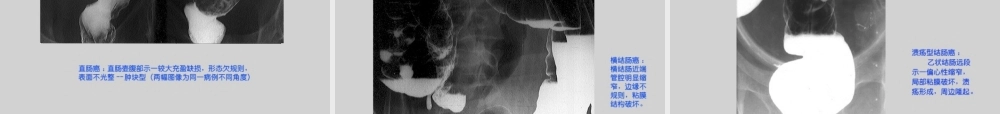

肠结核肠结核((TuberculosisofthesmallTuberculosisofthesmallintestineintestine))结核杆菌引起的肠道慢性特异性感染,常继发于肺结核,常与腹膜结核、肠系膜淋巴结结核并存。多见于青少年,40岁以下者占90%,女多于男。好发回盲部,占胃肠道的60-80%,其次是十二指肠、回肠、空肠。钡餐检查为重要诊断方法。概述感染途径感染途径经口摄入血行播散直接侵犯病理改变病理改变1、溃疡型:机体过敏反应强,出现干酪性坏死,形成溃疡,病变易侵及浆膜而导致粘连、瘘管、穿孔及脓肿形成。纤维组织增生可出现肠腔变形、狭窄。2、增殖型:反应弱,首先累及盲肠。以肉芽组织增生为主。肠壁增厚、肠管狭窄、变形,局部形成肿块。如有腹膜、肠系膜受累,可出现腹膜炎、肠粘连、腹水。临床表现临床表现起病缓慢,病程较长,常伴全身其他器官结核。常出现右下腹痛(隐痛、钝痛);如发生梗阻可出现绞痛、腹胀、肠蠕动亢进。排便习惯改变(腹泻与便秘交替)。查体:右下腹肿块------固定、境界不清。并发症:腹膜结核,肺结核,生殖器结核,肠梗阻,肠漏。XX线表现线表现溃疡型①粘膜紊乱、破坏。②肠管边缘不规则,有小刺状或锯齿状龛影。③管壁增厚,管腔不规则狭窄、变形,形态固定,近端肠管淤积、扩张。④肠道动力加快,服钡后2-5h钡头达乙状结肠,24h完全排空。⑤跳跃征(skipsign):病变段肠管痉挛、激惹,钡剂充盈不良,呈细线状,其上、下肠管充盈正常。增殖型增殖型①盲肠和升结肠肠腔不规则狭窄、缩短、僵硬。②粘膜皱襞粗乱。③多发小息肉状或较大的充盈缺损。④肠腔狭窄,近端扩张,激惹轻。⑤纤维增生、局部粘连、肠道动力减弱,表现为蠕动减弱,排空延迟,回肠呈郁积现象。⑥如结肠系膜受累,纤维挛缩,可出现盲肠及末端回肠牵拉上移。肠结核增殖型肠结核末段回肠肠结核肠结核末段回肠肠结核CTCT表现表现①限局性狭窄,肠壁轻度增厚,轮廓锯齿状,肠袋、皱襞消失、肠腔狭窄、肠袢僵直及肠管缩短,较对称,常引起小肠不全梗阻。②病变以回盲部为中心,肠壁轻度增厚,累及范围较长。③回盲部及盲升结肠变形较明显,肠管缩短、回盲部明显上移。回盲瓣明显缩窄或增宽。④口服造影剂CT扫描,回盲部常不能获得很好充盈,盲升结肠可呈细线状,而横结肠和小肠却能很好充盈,此征象类似钡剂造影检查时的“跳跃征”。肠腔轮廓不规则,肠腔变窄,肠壁增厚。结肠系膜内散在淋巴结影,无明显融合。结肠癌结肠癌(colorectalcarcinoma)(colorecta...